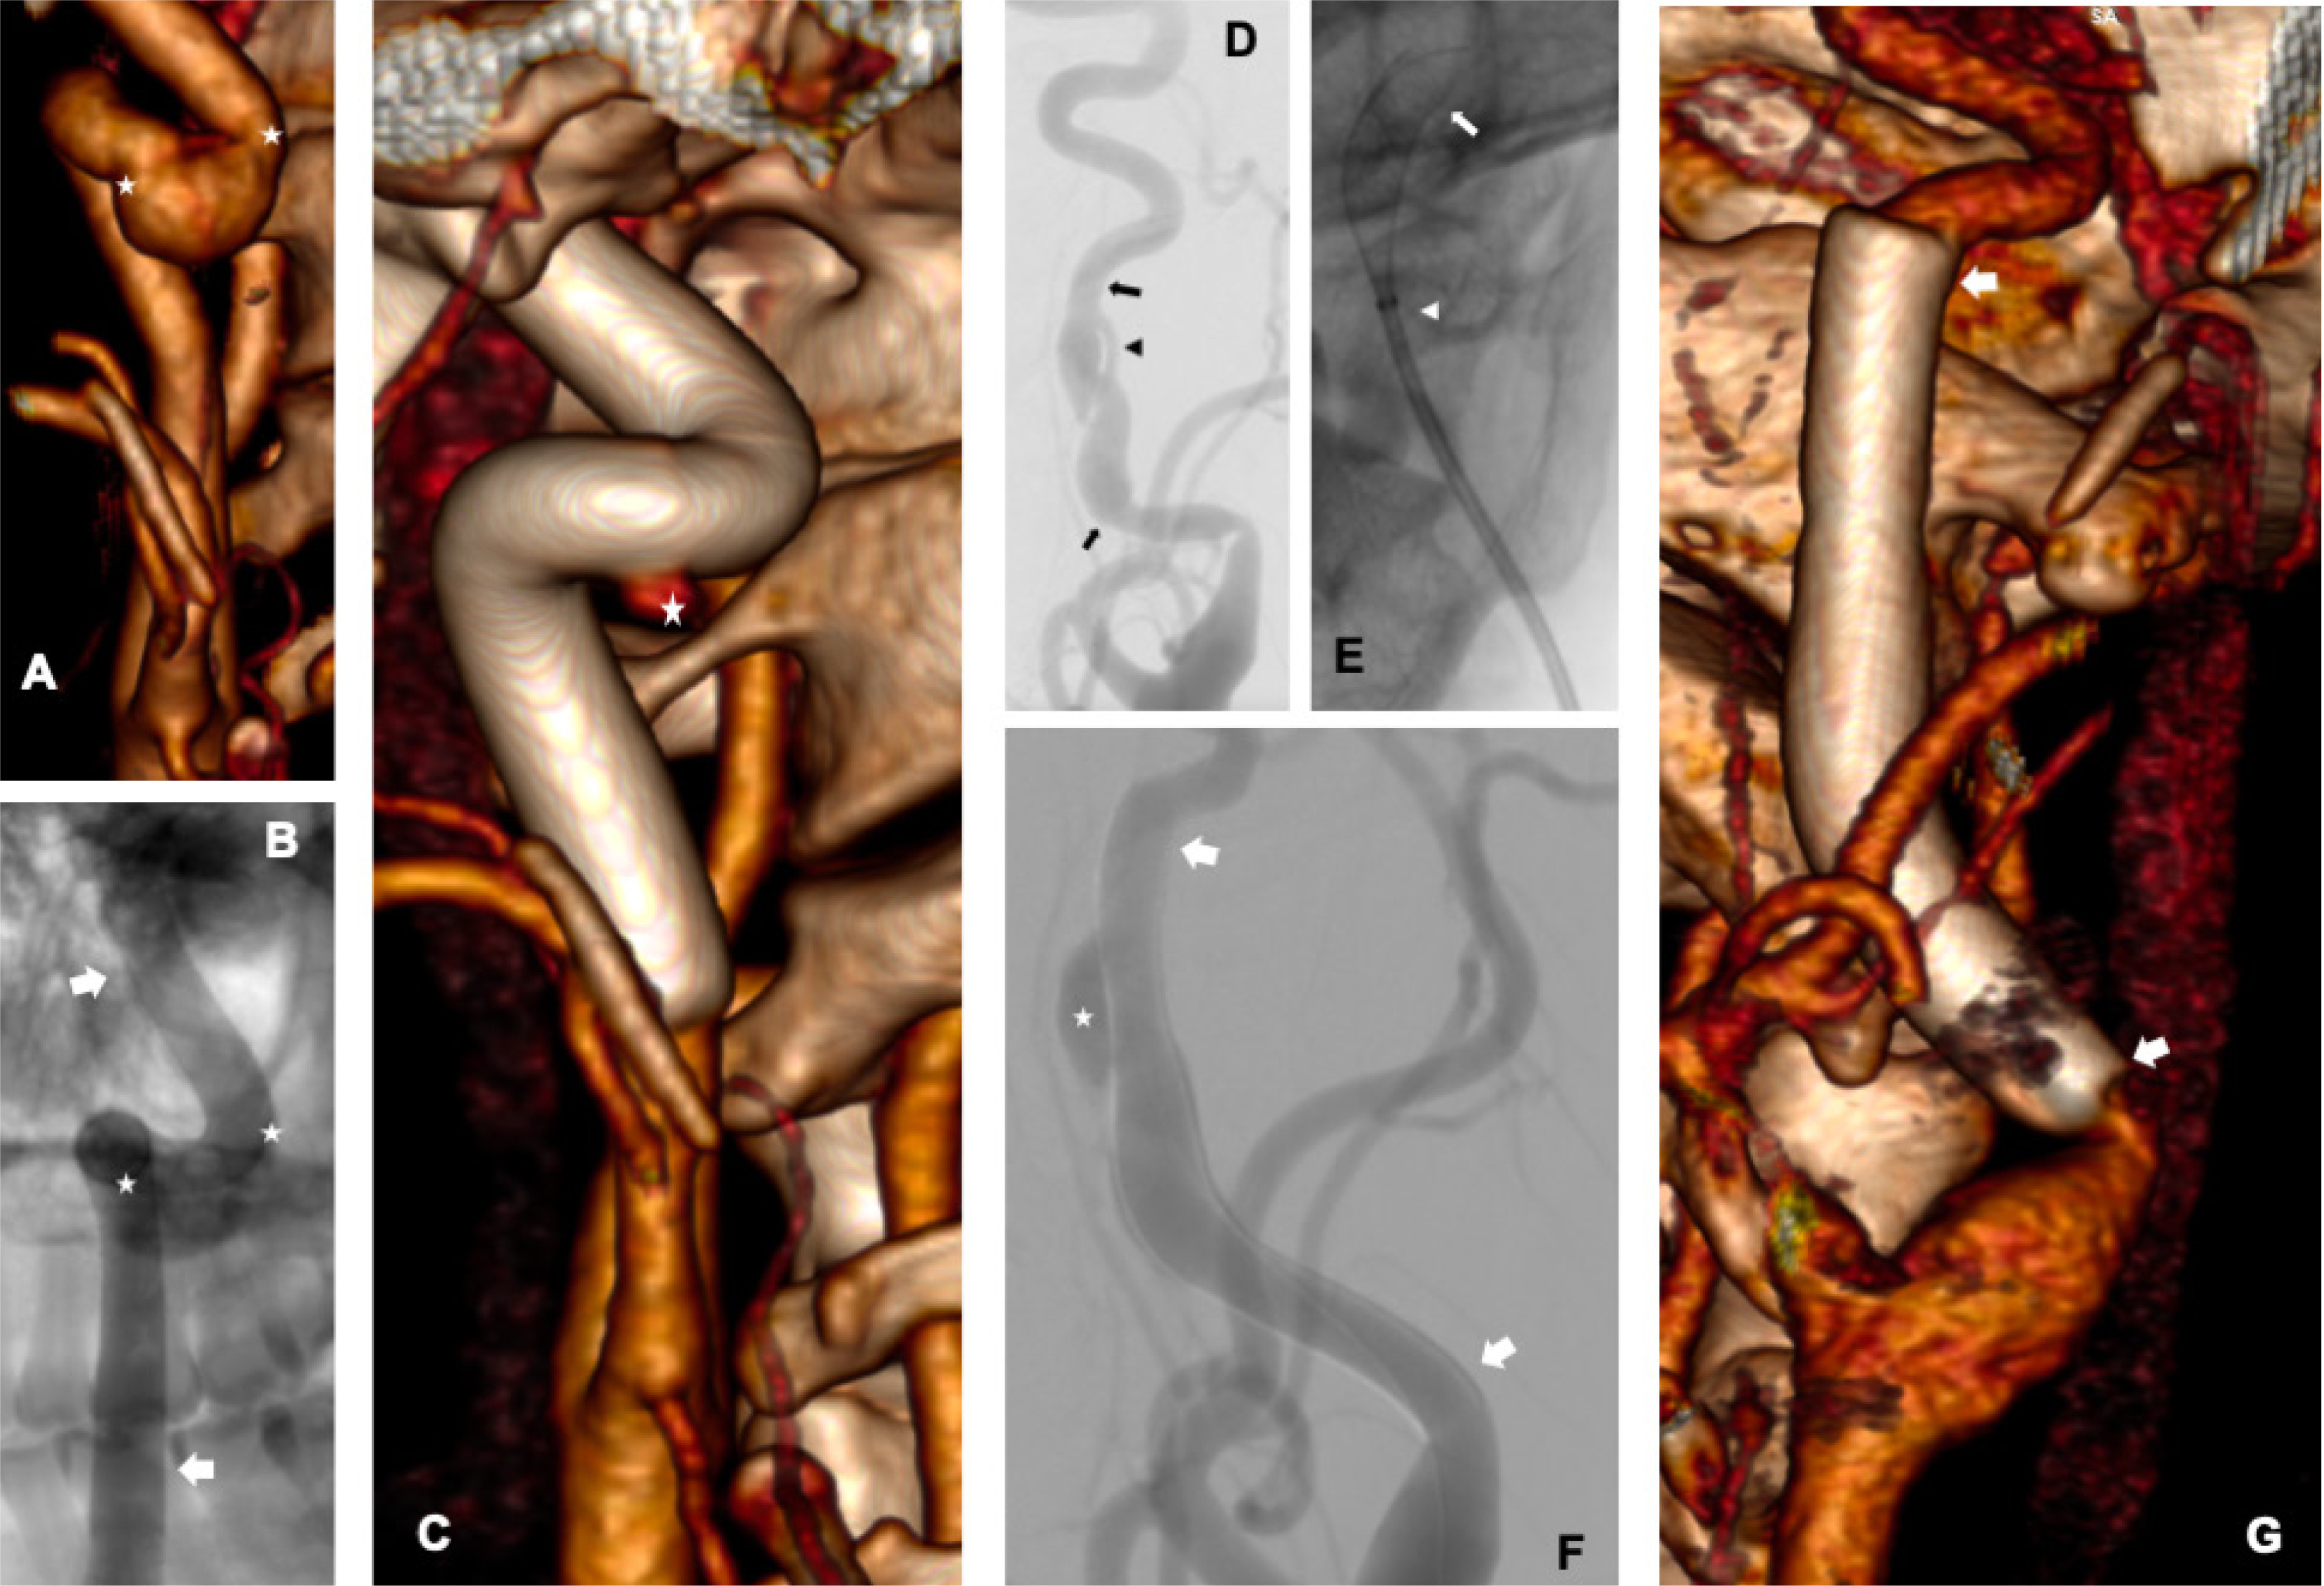

Stents were successfully implanted in all 4 patients. Stents completely covered the dissections and excluded pseudoaneurysms from the circulation (Figures 1 A–G). There were no new neurological events, in-hospital deaths, or other serious adverse event associated with the treatment. There were no new neurological events during the follow-up period. Repeat computed tomography (CT) angiographies in all 4 patients revealed complete coverage of pseudoaneurysms by the stents. There were no new lesions in the area of the previous dissection.

Figure 1

A – Computed tomography (CT) angiography of the right internal carotid artery – dissection is present in the segment between the bends, with a large pseudoaneurysm (asterisks indicate pseudoaneurysm); B – angiography after stent implantation showing persistent inflow to the pseudoaneurysm (arrows indicate the stent, asterisks indicate the pseudoaneurysm); C – repeat CT angiography – preserved artery shape, full coverage of the dissection, small inflow to the pseudoaneurysm (asterisk indicates residual, small flow to the pseudoaneurysm); D – angiography of the left internal carotid artery (arrows indicate the beginning and end of the dissection, arrowhead indicates the true lumen, next to it the pseudoaneurysm is visible); E – initial step of stent deployment (arrow indicates the beginning of the stent, arrowhead the end of the NeuroSlider catheter); F – angiography after stent implantation (arrows indicate the beginning and end of the stent, asterisk – the pseudoaneurysm); G – repeat CT angiography – complete coverage of the lesion, without inflow to the pseudoaneurysm (arrows indicate the beginning and end of the stent)